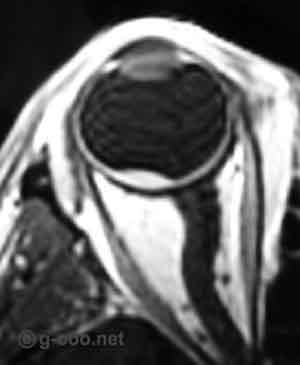

Hemangioma da coroideia pouco elevado do polo posterior do olho direito, de um homem de 50 anos de idade, difícil de  ver à observação do fundo do olho, mas facilmente identificável pela ecografia e pela Ressonância Magnética, aqui em ponderação T1, com sinal hiper-intenso em relação ao vítreo, e com grande captação de contraste.

Apesar de ter realizado tratamento com feixe de protões, mantém a visão de 100% passados 10 anos.